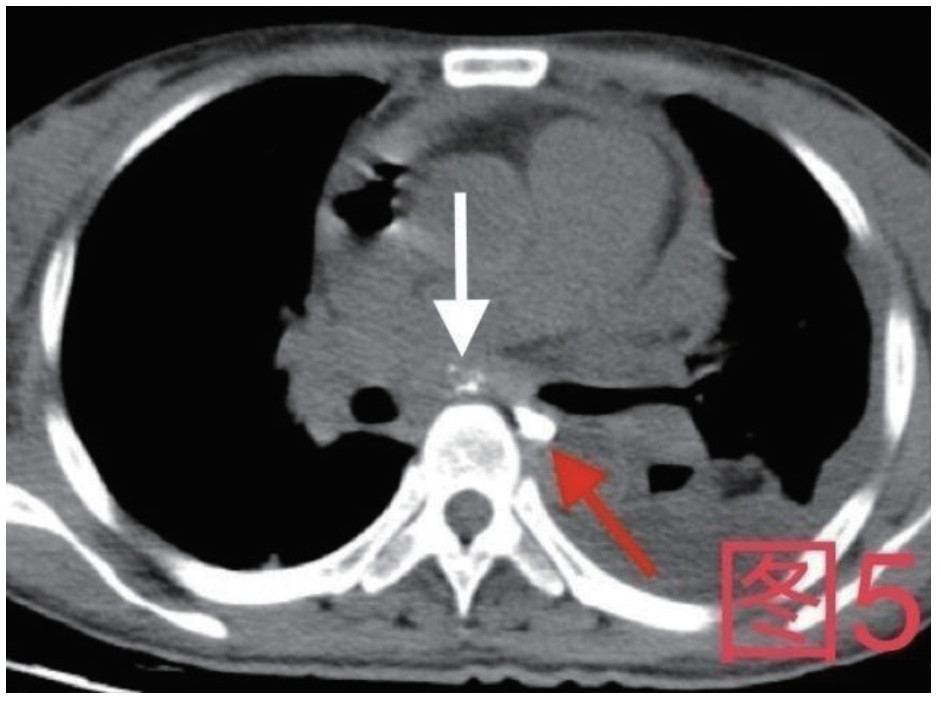

治疗经过:急诊予美罗培南0.5 g,1次/12 h抗感染,补液支持,心包引流等治疗措施,收住感染科后继续抗感染治疗,期间心包积液培养出白假丝酵母菌,加用氟康唑200 mg,1次/d, 口服,心包积液、左侧胸腔积液引流等措施,治疗10 d后复查胸部CT仍有中大量心包积液伴少许积气,纵隔积气;左侧少量胸腔积液,两肺叶间裂少许积液。对照前片(2020.10.26)心包积气及左侧胸前积液有增多,叶间裂积液新发,心包积液略有减少。右肺下叶感染,左肺下叶膨胀不全,较前右肺下叶感染有吸收,左肺下叶膨胀不全新发。考虑不能排除食管纵隔瘘,予口服碘海醇后胸部CT检查(图 3~6):约胸6椎体水平食管纵隔瘘,瘘口为相应水平食管壁右前方可能;胃镜(图 7):食道距门齿25 cm右后壁见一直径约1.0 cm凹陷,内有一小瘘口。胃镜下予钛夹2枚夹闭瘘口(图 8),同时植入空肠营养管。至此患者病情明确诊断食管心包瘘,患者经以上治疗后心包积液、胸腔积液逐渐减少,于11月13日拔除心包及胸腔引流管,因患者签字回当地就诊,予口服莫西沙星、氟康唑带药出院,出院后随访,患者未回当地医院治疗,仅在家中继续空肠营养管饲喂及口服抗菌药物治疗。

| 图 5 患者卧位第2次口服15 mL碘海醇后,白色箭头所指为纵隔内碘海醇,红色箭头为食管内碘海醇 |